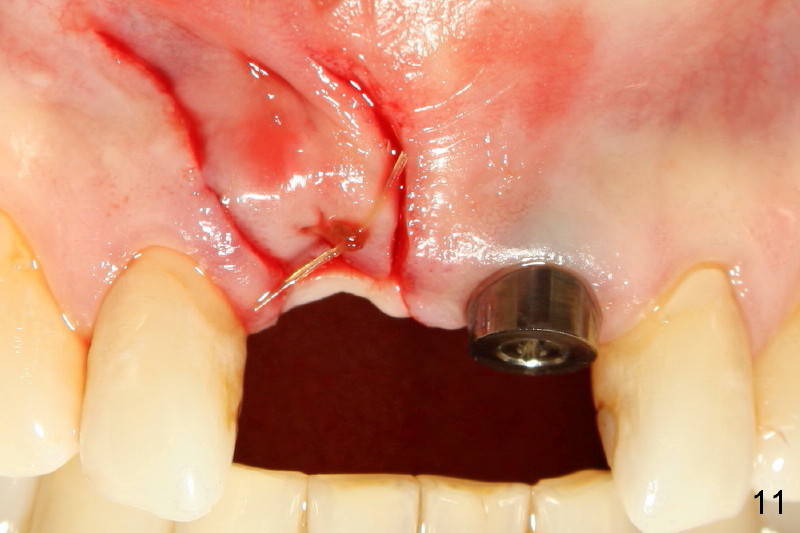

The implant at the site of #8 was removed without difficulty, 3 months after its placement.  Apical granulation tissue was removed, although not much.  The buccal plate remains intact.  The socket was copiously irrigated with normal saline with Tetracycline. Buccal and palatal flaps were raised with periosteum scored.  The wound was closed (Fig.11).

Thanks for calling me (immediately before I saw the patient) and providing advice on removing the implant. In fact the procedure was done smoothly, basically according to your suggestion, including approximating the socket (Fig.11). Will the infection dissolve in 6 weeks before redoing implant placement? The buccal plate is intact, and must be thin.